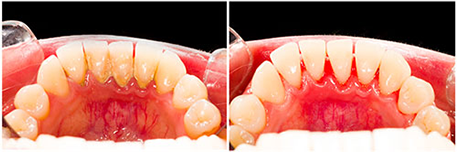

Periodontal disease is a chronic gum infection caused by plaque resulting in loss of bone support around the roots of teeth. Plaque is a thin film of bacteria that forms on teeth. Plaque converts to tartar if not cleared from teeth after 24hrs. Tartar irritates gums leaving them red, swollen and bleeding readily.

Eventually the gums peel away from teeth and create small pockets between the teeth and gums, slowly continuing to also destroy the supporting bone. Severe loss of the supporting bone is what loosens up teeth and make them incapable of functioning properly. Periodontal disease is often painless and will go undetected until bone loss is so severe that teeth are so loose they need to be extracted.

- Bleeding gums when you brush or floss

- Red, swollen, tender gums

- Gums that have receded or shrunken away from teeth

Treatment usually involves a thorough scaling and root planning to remove plaque and built up tartar, thus allowing healthy gums tissues to reattach to root surfaces of teeth. Clean surfaces of teeth must be maintained by meticulous home oral hygiene and routine check-ups and cleaning. Advances stages of periodontal disease however, may require gum surgery, grafting, and/or extractions.